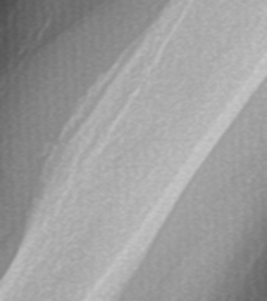

4. Pseudotumor Deltoideus

This normal variant appears as a prominent deltoid tuberosity with cortical radiolucency and irregularity. This finding occurs due to the insertion of the deltoid tendon at the deltoid tuberosity. This non-pathologic anatomic variant can be confused with malignancy, due to the irregular lucent appearance and the simulation of an aggressive periosteal reaction. A knowledge of the classic location and appearance should allow for proper diagnosis and avoidance of unnecessary imaging or biopsy.